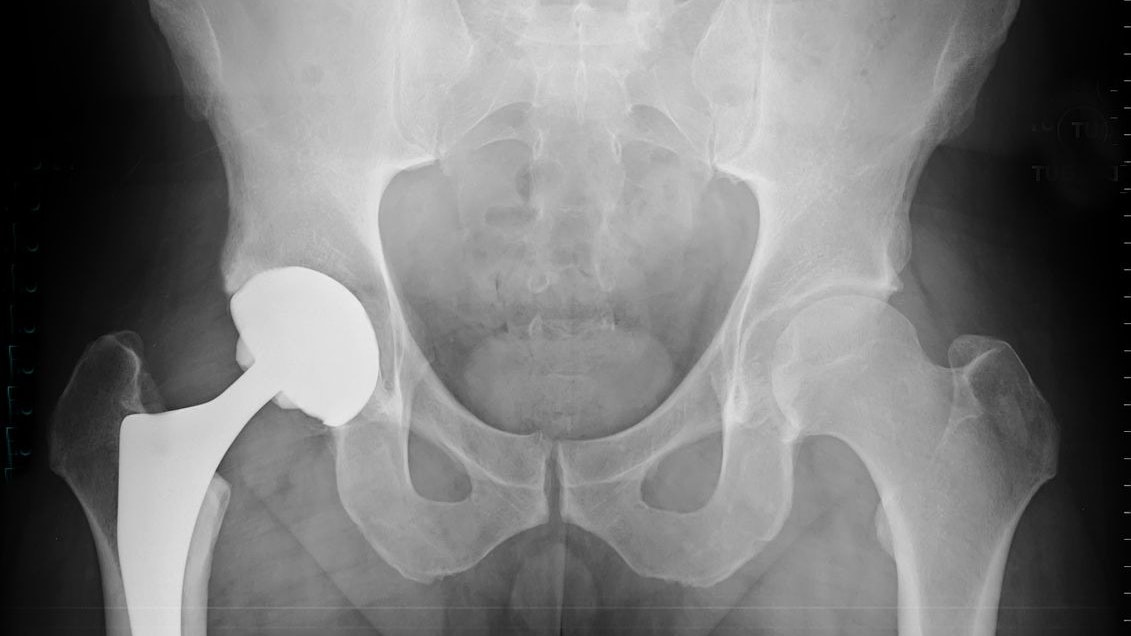

Tracey O'Neill litt sie jahrelang unter gesundheitlichen Problemen (Symbolbild).